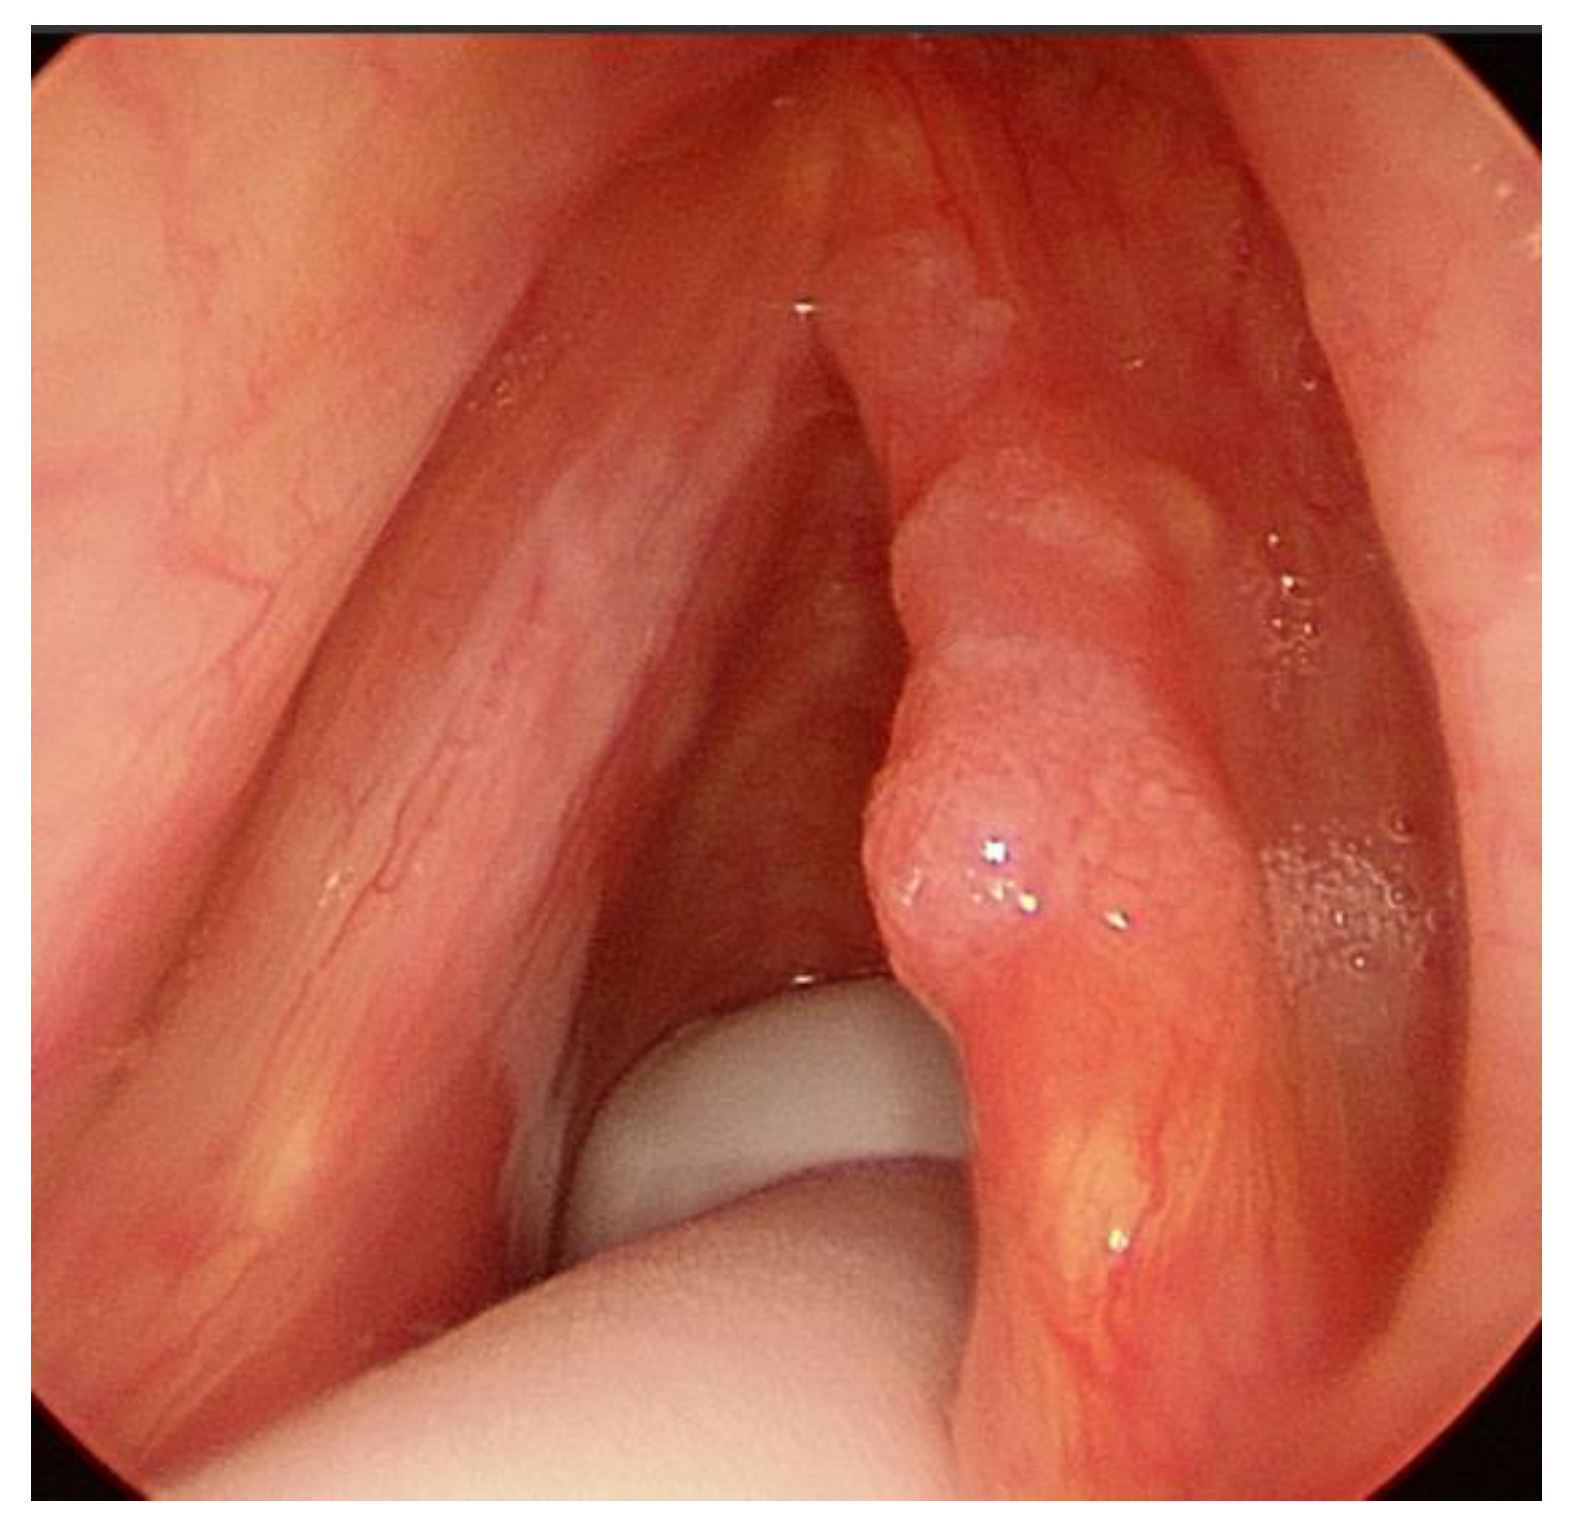

- T1a, tumor limited to one vocal cord, without AC involvement, with normal vocal cord mobility (Figure 1);